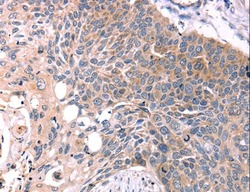

Supportive validation

- Submitted by

- LSBio (provider)

- Main image

- Experimental details

- Immunohistochemistry of Human ovarian cancer using KISS1R Polyclonal Antibody at dilution of 1:15.